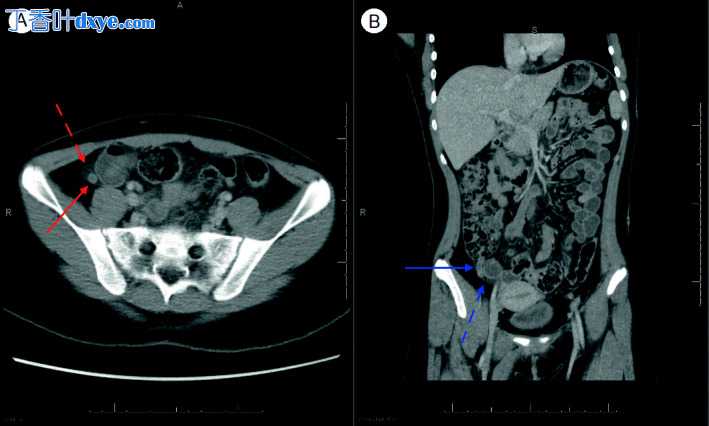

图 1

CT 腹部/骨盆。 (A) 阑尾(红色实线箭头)壁厚>3mm。 腔内空气不足,阑尾积液深度>2.6mm,高密度。 红色虚线箭头显示阑尾周围脂肪绞合。 (B) 直径 8 毫米(蓝色实线箭头)伴有炎症性脂肪绞合(蓝色虚线箭头),在盲肠周围最为明显

一夜之间,患者持续发热和心动过速。她还报告说 RLQ 疼痛增加,并表现出新的腹部反跳痛。主治儿科放射科医生对先前 CT 的回顾得出结论,该影像学与急性阑尾炎一致,因为阑尾扩张,测量 8 毫米,阑尾黏膜轻度增强和邻近肠系膜脂肪绞合(图 1)。与儿科手术重新讨论了患者的护理,多学科团队一起无法明确排除阑尾炎作为并发病理学。虽然 MIS-C 的诊断通常需要排除其他病因,但人们认为她可能同时患有阑尾炎和 MIS-C。阑尾炎的经验性治疗以哌拉西林-他唑巴坦开始。手术团队审查了持续使用抗生素与诊断性腹腔镜检查和阑尾切除术的非手术治疗的风险和益处。选择手术治疗。获得超声心动图以评估心脏受累情况,显示心脏功能正常,冠状动脉无扩张。住院第 2 天,她在急性病床上保持稳定,并要求静脉注射免疫球蛋白 (IVIG) 和阿司匹林治疗 MIS-C。然而,考虑到手术可以将她带到手术室的时间,她首先接受了诊断性腹腔镜检查和阑尾切除术。发现她的阑尾基本正常,没有炎症提示阑尾炎(图 2)。由于外科医生对阑尾炎的术中“眼球”评估并不完美,并且在进行腹腔镜检查时阑尾切除术的风险很低,因此决定完成阑尾切除术。组织学发现仅显示轻度慢性浆膜炎症和水肿间皮;它没有显示阑尾炎的透壁急性炎症诊断。停用哌拉西林-他唑巴坦,患者返回急诊室进行术后监测,并使用 IVIG 输注(2 g/kg)和阿司匹林(81 mg)进行 MIS-C 治疗。